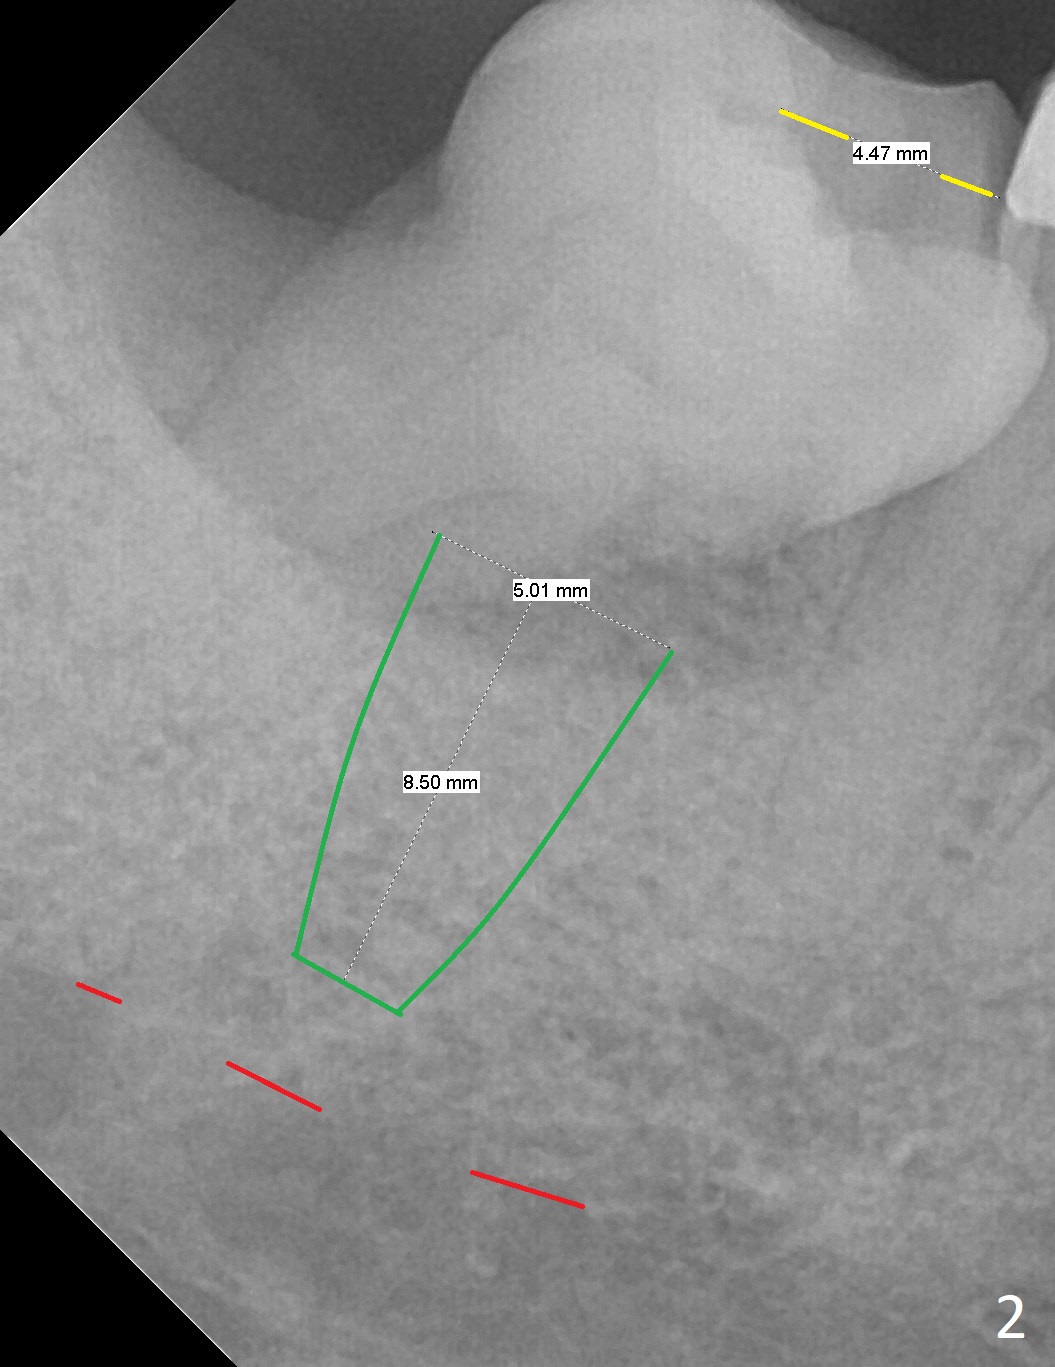

Parallel to 1st Molar

A 60-year-old man has chronic periodontitis, bruxism and malocclusion, e.g., #18 mesiolingual inclination (under occlusal trauma, Fig.1). The lingual pocket is deep with severe bone loss. After extraction, use implant positioner to gauze the size of the socket. Initiate osteotomy as mesial as possible and parallel to the 1st molar (Fig.2,3). Bone density is expected to be high. Prepare soft (1-piece) and hard (IS) tissue-level implants. The tooth remains loose 2 years later, although the patient is asymptomatic (Fig.4). Finally the tooth is symptomatic because of root tip fracture (Fig.5). Use drills with 7.3 mm stop for 4.5 or 5.0x8.5 mm implant free hand (Fig.6). The exposed implant will be covered with sticky bone (PRFx2). Prepare temporary and cemented abutments to hold bone graft in place.